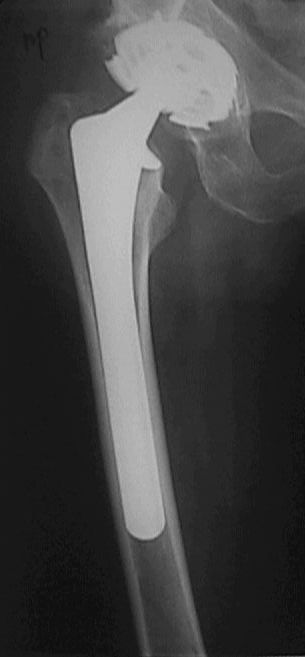

Больной оперирован в конце марта 2003 НИИТО г. Новосибирск. Не замечен перелом бедра р-ма 1.- 2 . (сделанных в НИИТО). Больному рекомендовали ходить приступая на конечность, отмечает усиление болей, появление укорочения.На контрольных рентгенограммах 19.05.03 рис 3 имеется перелом бедра со смещением, появлением периостальной мозоли. Больной ходит на костылях, приступая на конечность. Сгибание в т\б суставе 90 гр , сгибание в коленном суставе до 90 гр в положении стоя на костылях.Есть несколько вариантов.1. Провести открытую репозицию фиксацию пластиной с проведением винтов на уровне ножки протеза через кортикальный слой.2.Провести открытую репозицию фиксацию винтами с межфрагментарной компрессией. Думаем, как выполнить репозицию перелома по длине.3. Наложить кокситную повязку до окончательного сращения перелома4. Провести скелетное вытяжение репозицию.Сергей ЗыряновНовосибирская область г. Куйбышев ЦРБ

Рис-2 сделаны в НИИто через неделю после операции